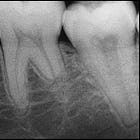

Which to me is evidenced by the fact that this artificial tooth movement is almost always followed by some root resorption as i wrote about here: